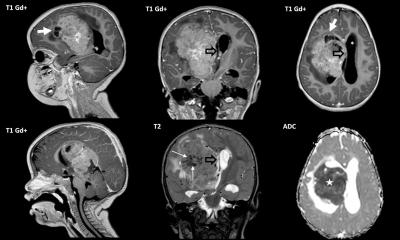

The four recognized molecular subgroups are the SHH (sonic hedgehog) and Wnt (wingless) pathways, and two non-SHH and non-Wnt subtypes named Group 3 and Group 4, in the absence of better names. Some imaging correlates can give a clue as to the phenotypic or genotypic type. The SHH subgroup is the second largest group of MBs, and is typically more common in the lateral cerebellum than in the midline. “If it´s in the lateral cerebellum and has solid enhancement, most of these are going to SHH,” Osborn stated. Wnt may be the smallest group of MBs but is has the best prognosis; more than 90% of these patients will survive in the long term. An imaging surrogate marker for these tumours is their typical location in the CPA or cerebellar peduncle. This information is significant because, since it has very good prognosis, children may be spared chemotherapy and only undergo surgery. Group 3 MBs have terrible survival and most of them are located right in the midline. However there is nothing that distinguishes them on imaging as of today. Group 4 MBs have intermediate survival and are mainly present in the midline; they tend to have minimal or no enhancement.